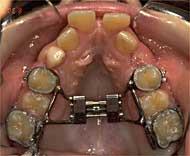

C) "Espansore palatale":allarga rapidamente un palato troppo stretto, in modo da creare spazio in caso di denti affollati (oltre che migliorare la "respirazione nasale"...)